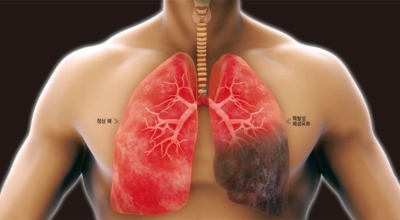

폐렴은 폐의 감염으로 인해 발생해요. 대부분의 감염은 박테리아나 바이러스에 의해 발생하지만 종종 원인을 찾을 수 없어요. 감기나 독감에 의해 유발될 수 있고, 이로 인해 세균이 폐에 접근할 수 있어요. 세균성 폐렴은 폐렴구균 박테리아에 의해 발생할 수 있어요. 이것은 가장 심각하고 잠재적으로 생명을 위협하는 유형의 폐렴 중 한가지이예요.

폐렴을 유발하는 다른 유형의 박테리아는 헤모필루스 인플루엔자와 모락셀라 카타랄리스 이지요. 바이러스성 폐렴은 여러가지 바이러스에 의해 발생해요. 가장 흔한 것은 인플루엔자 바이러스, 인간 아데노바이러스 또는 호흡기 세포융합 바이러스이지요.

초기에 가벼운 기침으로 시작해 호흡하는 것조차 힘들어지게 되는데요 폐에 발생한 염증으로 인해서 폐의 신전성이 감소하고, 폐를 구성하는 폐포 세포가 망가져 적정 수준의 산소를 보관하지 못하기 때문에 호흡곤란이 유발될 수 있어요.